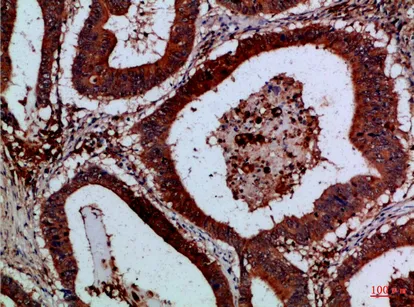

Reg IV Rabbit Polyclonal Antibody

Cat: APRab16998

Size1:50μl Price1:$118

Size2:100μl Price2:$220

Size3:500μl Price3:$980